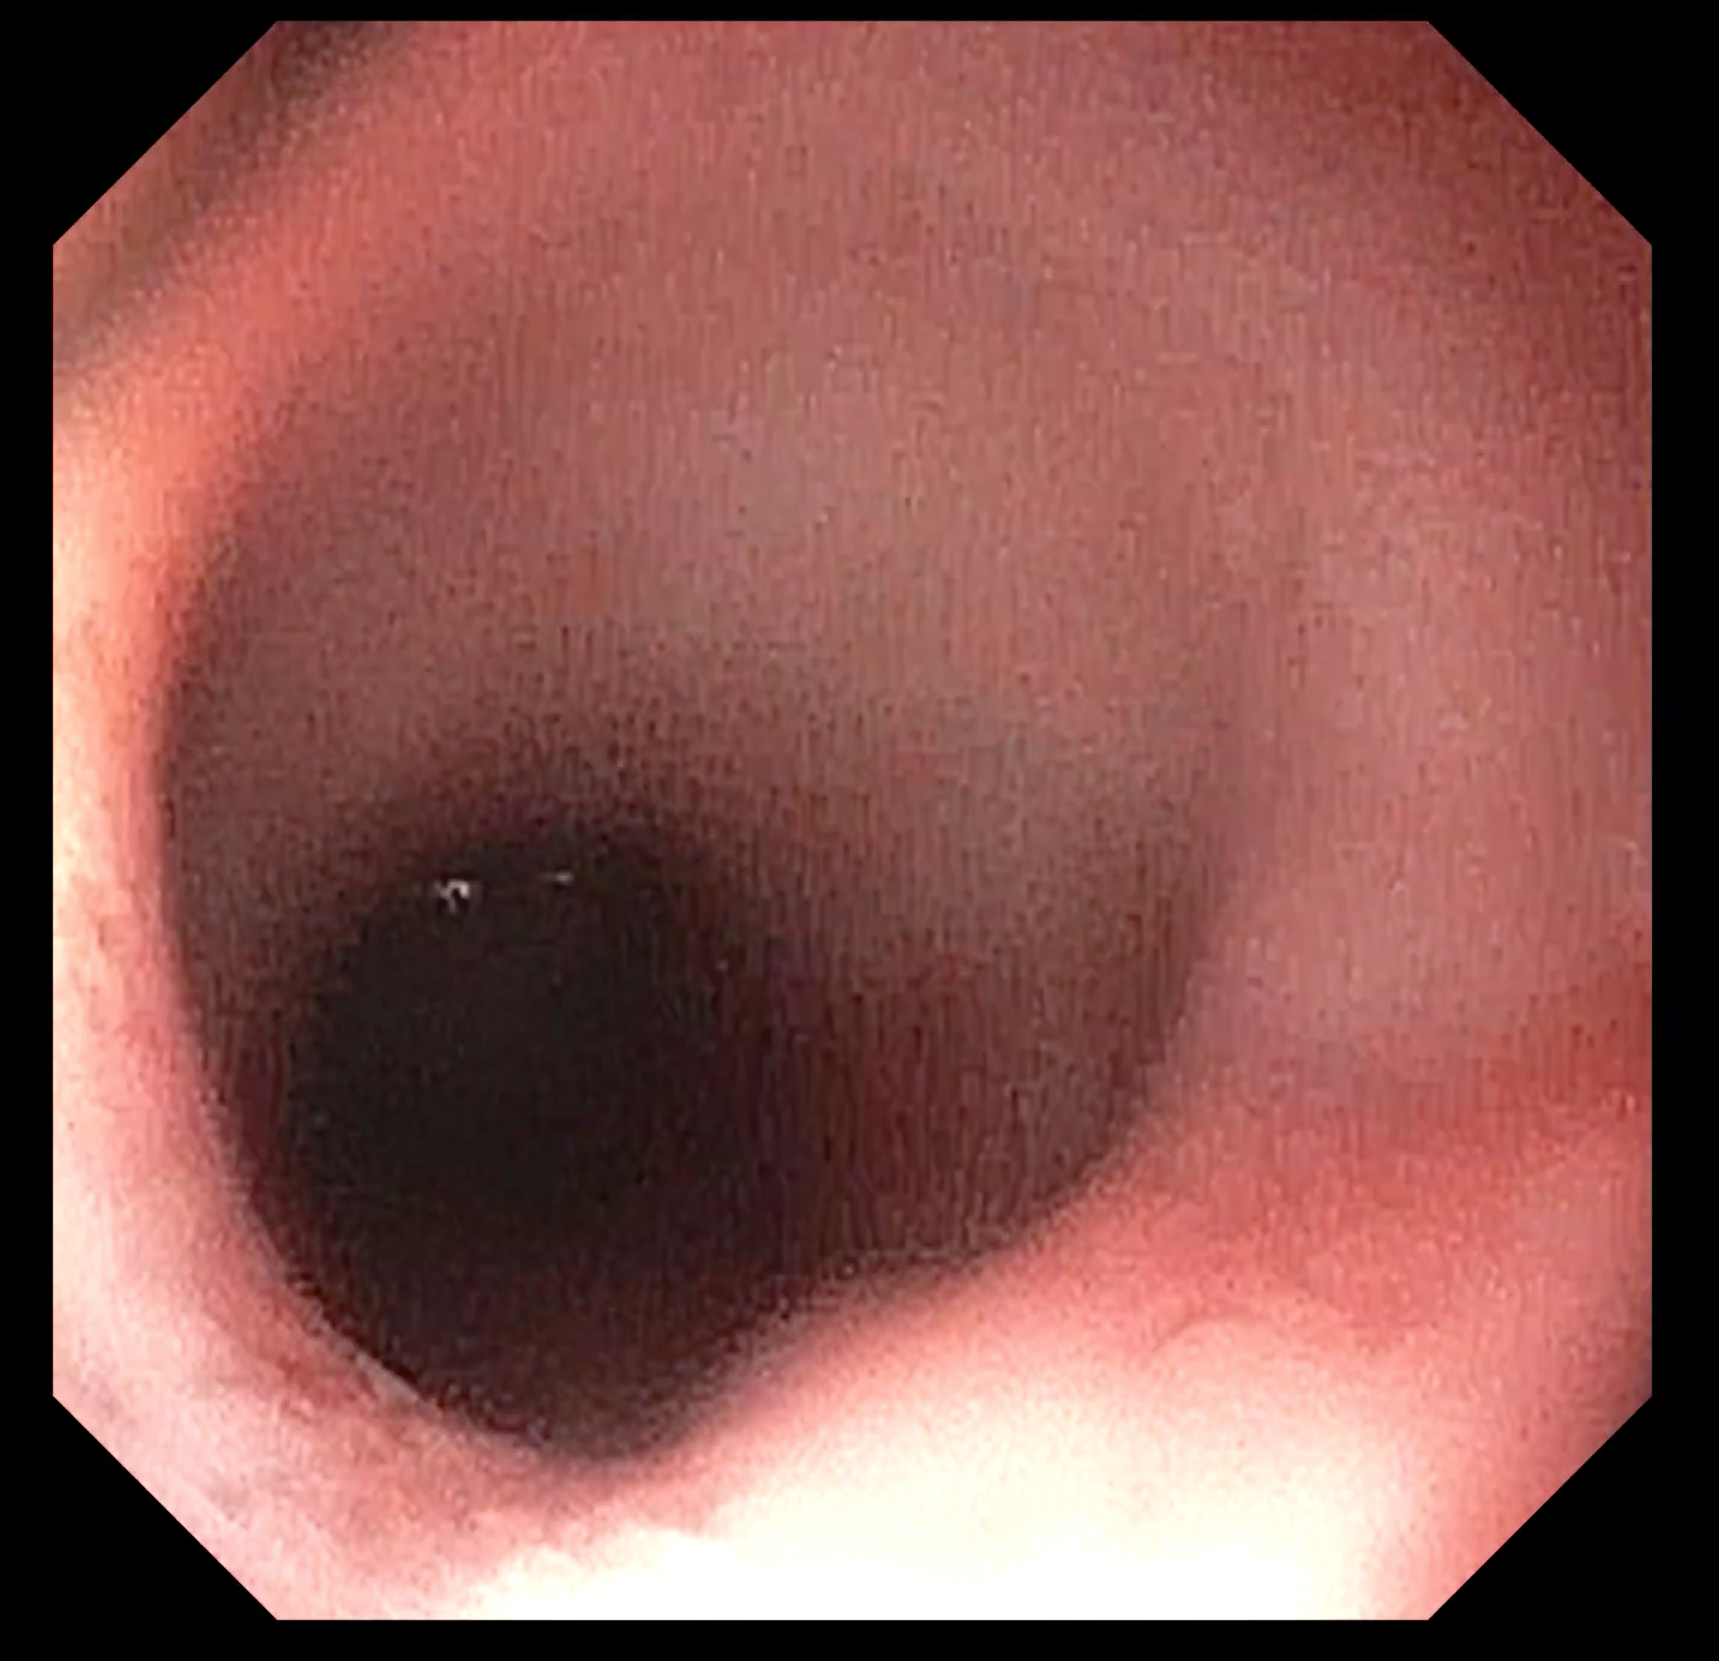

内視鏡カメラで腸の観察を行っている写真です